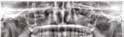

1. ábra: Megfelelő szájhigiénia – panorámaröntgen. 2. ábra: A 2.5, 2.6 és 2.7-nek megfelelő terület a röntgenfelvételen.

és jelentős mobilitással rendelkezett. A radiológiai vizsgálat után egyértelműen látszódott, hogy a fogon még nem végeztek gyökérkezelést. A 2.6-os és 2.7-es fogaknak megfelelő területen az arcüreg kiterjedése jelentős volt, vertikális csontmennyiség szignifikánsan csökkent (1. és 2. ábra).